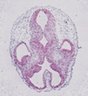

HDBR Atlas: Gene Expression in Early Human Development

Immunohistochemistry, immunofluorescence and RNAscope analysis in early human development from 3 to 19 weeks post conception.

Organism: Homo sapiens

Study Type: protein localization

Study Type: in-situ hybridization assay

Imaging Method: bright-field microscopy

Imaging Method: fluorescence microscopy